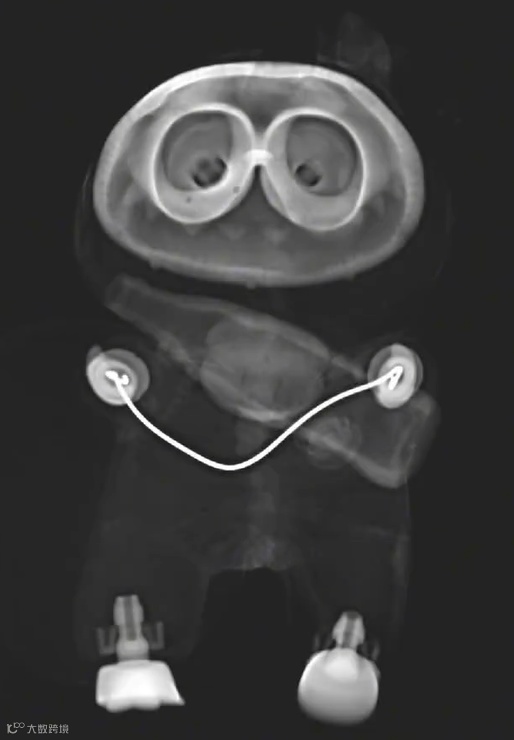

各款labubu X线图像大赏

接下来是各款labubu X线图像大赏,请准备查收!

还有给拉布布做矫正、带牙箍的: